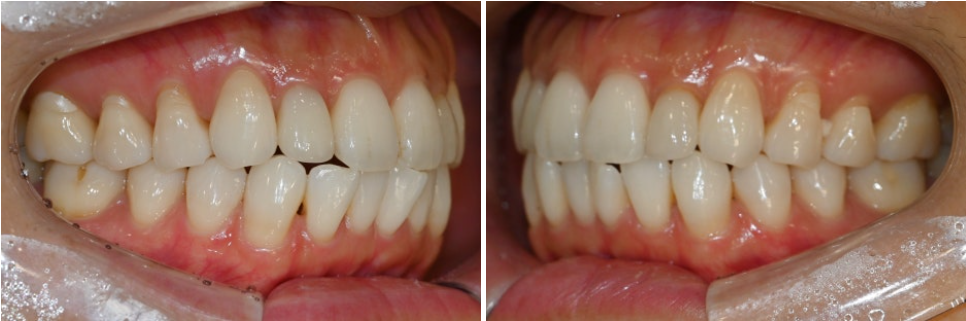

체크했을 때 어금니쪽은

배열이 좋고 잘 맞물리는 편입니다.

그러나 앞니는 절단면끼리 일자로

타이트하게 맞물리는 3급 부정교합인

절단교합 직전에 이르는 상태였습니다.

절단교합은 치아의 마모와 균열을

발생시킬 가능성을 높입니다.